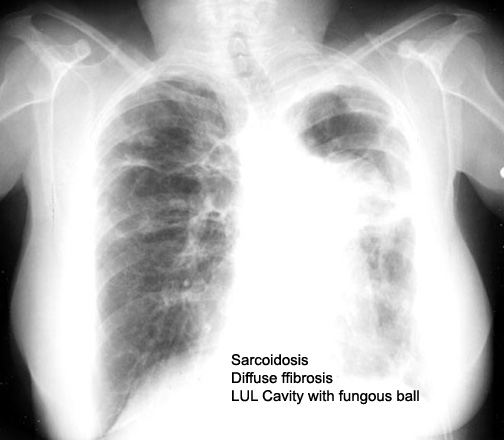

Case 19 Labeled Image What are the causes for bilateral upper lobe cavitary disease?